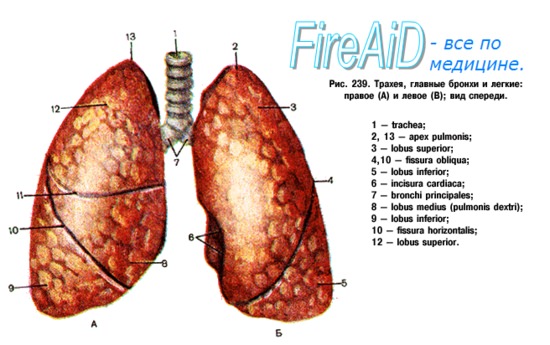

Анатомические изображения сегментов легких различных животных

Раздел: Другие животные